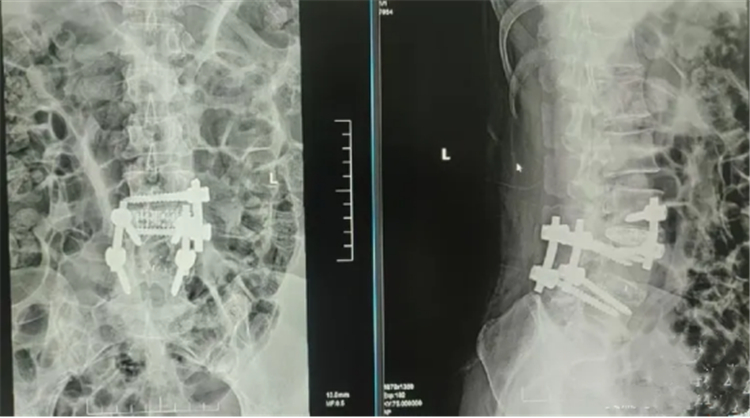

术前影像资料

在长沙泰和医院脊柱外科,留日博士、学科带头人宋西正教授接诊后,通过详细查体和反复阅片,诊断李女士患上的是腰椎融合术后邻椎病(ASD)。通俗来说,原本被固定融合的节段不再活动,导致相邻的腰3/4和腰5/骶1节段长期承受过大压力,进而出现退变,引发症状。

针对李女士同时存在两个相邻节段病变的情况,宋西正教授团队进行了全面评估。团队认为,若采用传统开放手术,需要行长节段固定融合,创伤较大。经讨论,团队决定为其制定一站式的微创联合手术方案,即一次麻醉下,结合应用椎间孔镜技术与侧方OLIF微创技术,分别处理腰5/骶1和腰3/4两个问题节段。